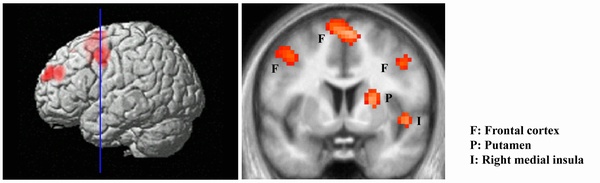

To compare their present results with their previous ones on romantic love, Zeki and Romaya specifically studied hate directed against an individual. Seventeen subjects, both female and male, had their brains scanned while viewing pictures of their hated person as well as that of neutral faces with which they were familiar. Viewing a hated person showed activity in distinct areas of the brain that, together, may be thought of as a ‘hate circuit’.

The ‘hate circuit’ includes structures in the cortex and in the sub-cortex and has components that are important in generating aggressive behaviour, and translating this into action through motor planning, as if the brain becomes mobilised to take some action. It also involves a part of the frontal cortex that has been considered critical in predicting the actions of others, probably an important feature when one is confronted by a hated person.

The subcortical activity involves two distinct structures, the putamen and insula. The former, which has been implicated in the perception of contempt and disgust, may also be part of the motor system that is mobilised to take action, since it is known to contain nerve cells that are active in phases preparatory to making a move.

Clusters of activation for the contrast Hated face>Neutral faces. The statistical threshold was set at p≤0.05 at the cluster level, corrected for multiple comparisons, with an underlying voxel-level threshold of p≤0.00025, as displayed.